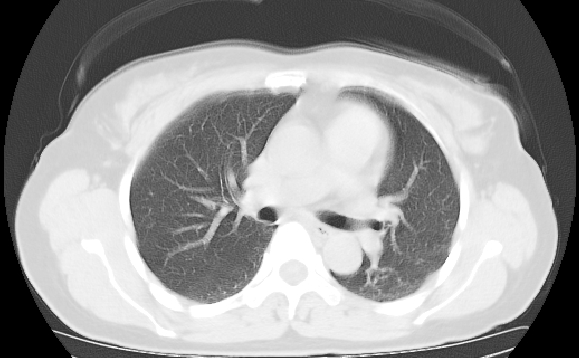

标题: CT25227:背部疼痛伴双侧胸壁痛2月,食欲差。 [打印本页]

标题: CT25227:背部疼痛伴双侧胸壁痛2月,食欲差。

肺结核并胸椎结核?请各位高手指教。

用椎体的条件来扫胸椎呀!考虑1左侧胸膜小结节形成2椎体结核并冷脓肿形成

左肺结核灶,胸椎结核并冷脓肿。

左肺结核灶,胸椎结核并冷脓肿